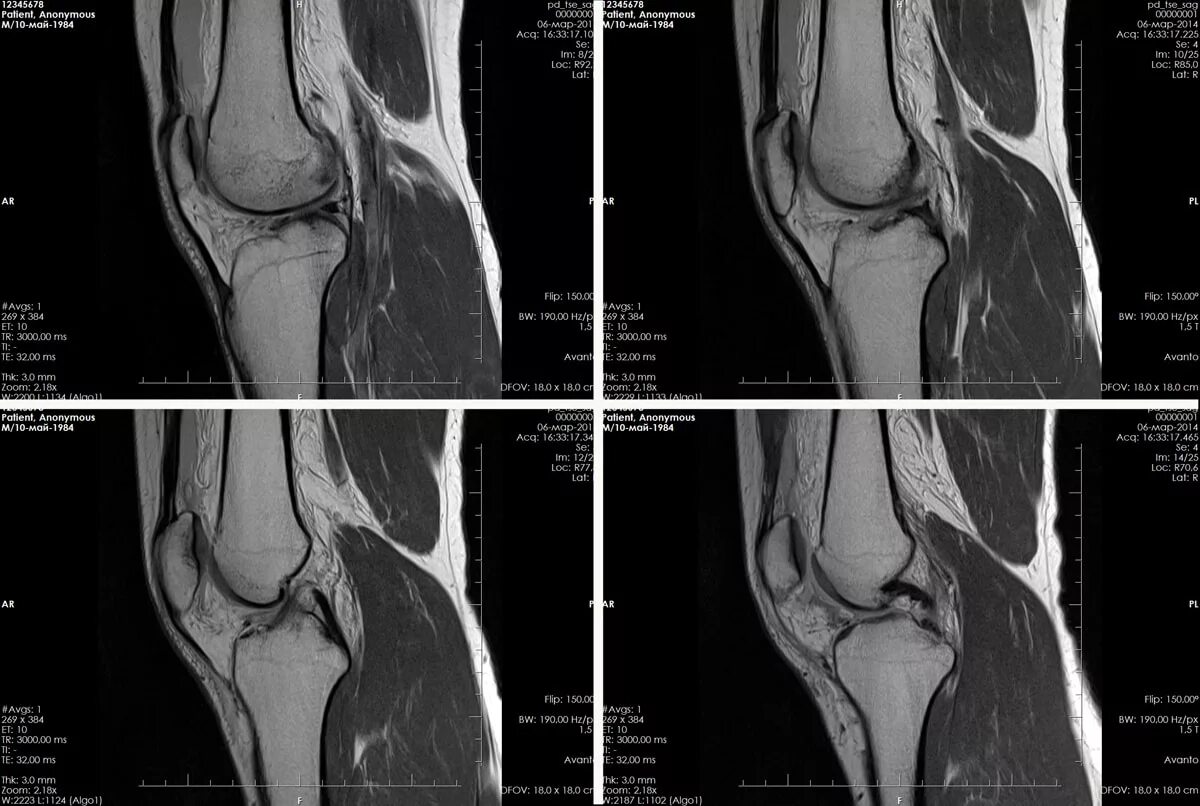

Мрт коленного сустава как проходит